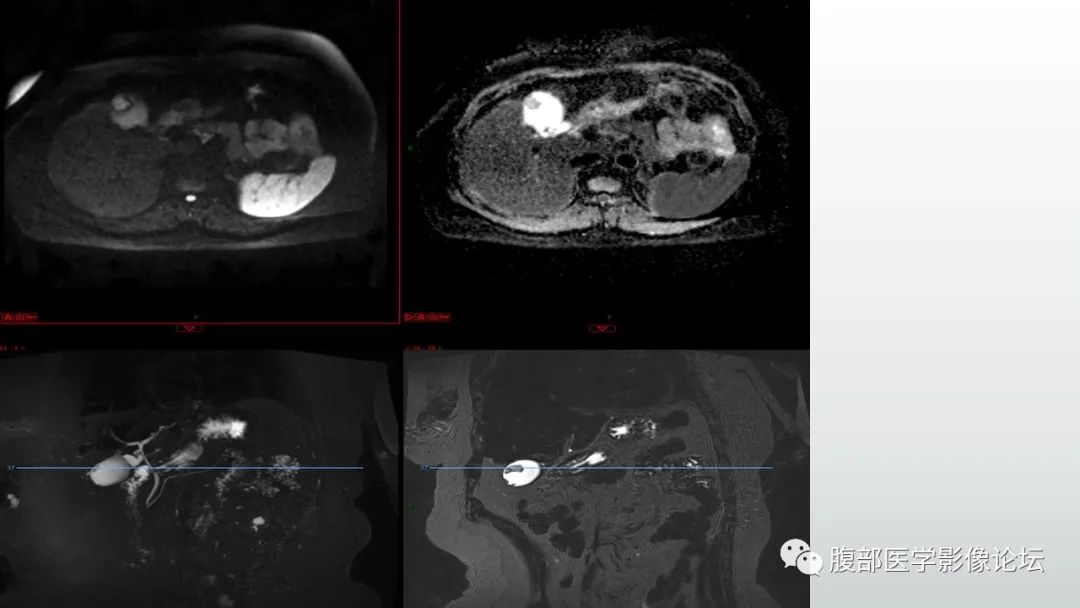

【病例】胆囊管状腺瘤1例CT及MR影像表现-5

【病例】胆囊管状腺瘤1例CT及MR影像表现-6